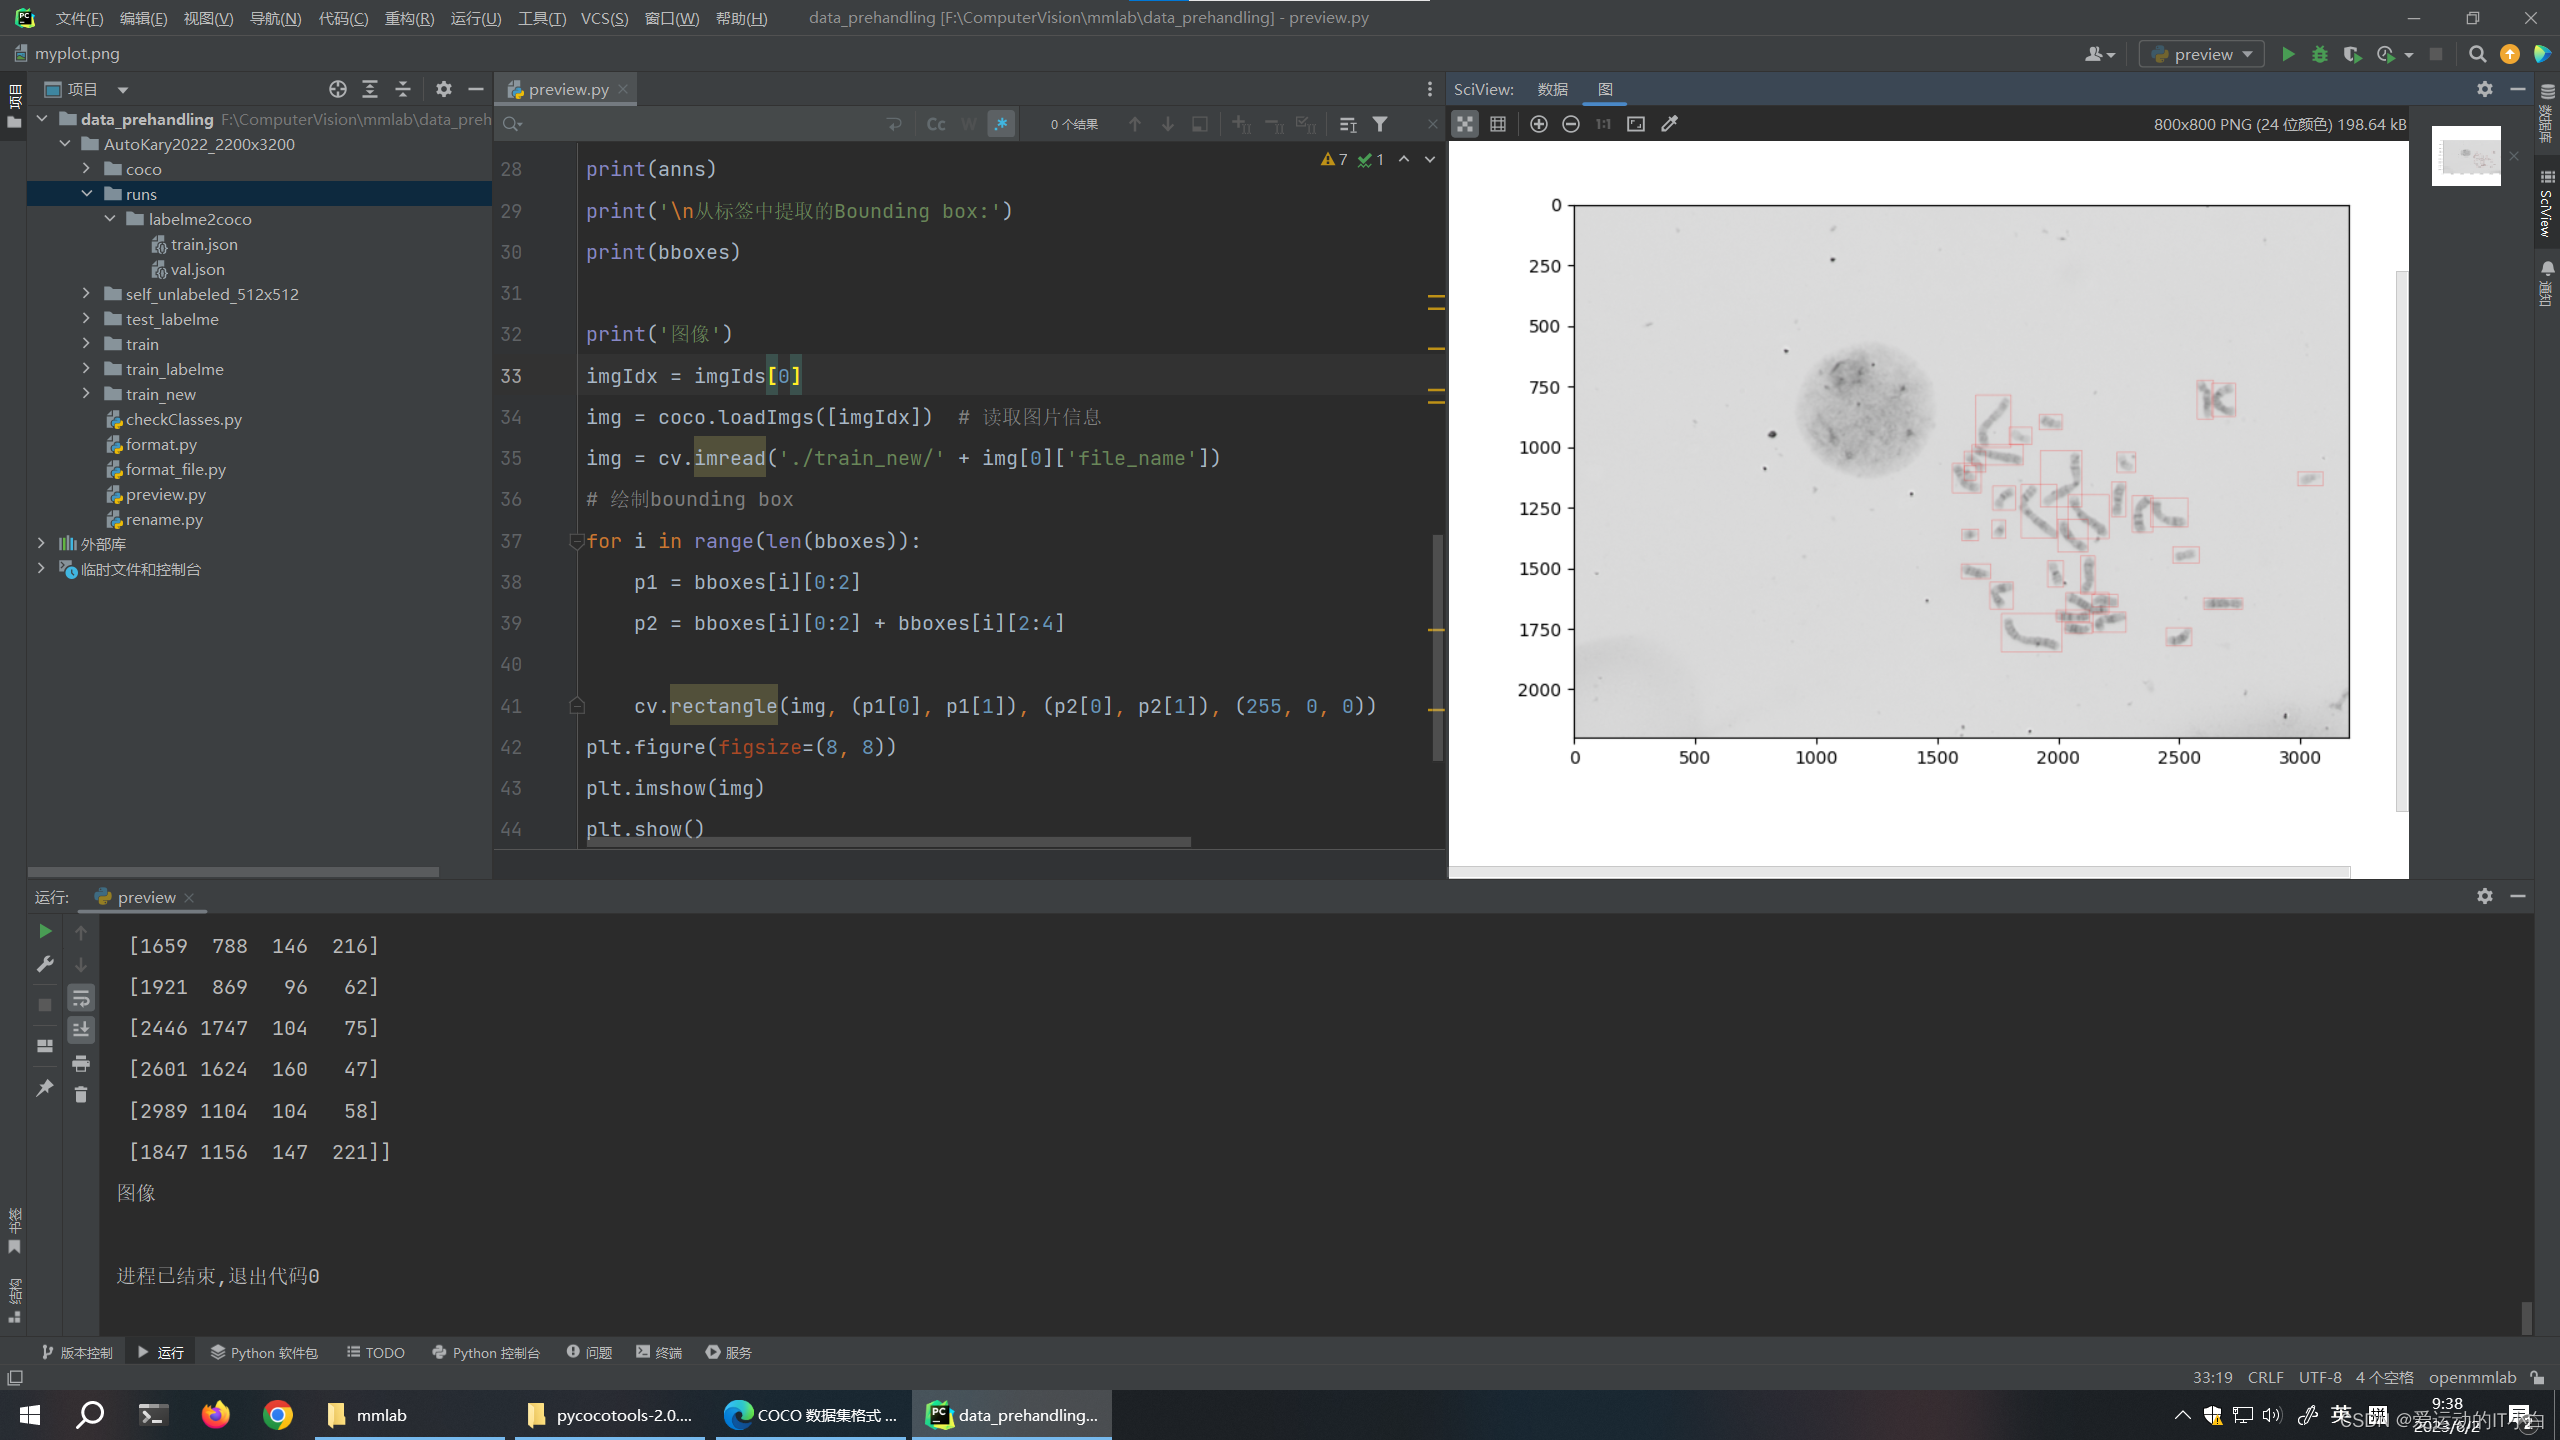

可视化预览处理好的COCO数据集

from pycocotools.coco import COCO

import numpy as np

from matplotlib import pyplot as plt

import cv2 as cv

# 加载COCO格式的标注文件

coco = COCO('./runs/labelme2coco/train.json')

imgIds = coco.getImgIds() # 获取所有的image id,可以选择参数 coco.getImgIds(imgIds=[], catIds=[])

imgIds = coco.getImgIds(imgIds=[0, 1, 2]) # 获得image id 为 0,1,2的图像的id

imgIds = coco.getImgIds(catIds=[0, 1, 2]) # 获得包含类别 id 为0,1,2的图像

annIds = coco.getAnnIds(catIds=[0, 1, 2]) # 获得类别id为0,1,2的标签

annIds = coco.getAnnIds(imgIds=imgIds[0]) # 获得和image id对应的标签

catIds = coco.getCatIds(catNms=['0']) # 通过类别名筛选

catIds = coco.getCatIds(catIds=[0, 1, 2]) # 通过id筛选

catIds = coco.getCatIds(supNms=[]) # 通过父类的名筛选

print('类别信息')

cats_name = coco.loadCats(ids=catIds)

print(cats_name)

print('\n标签信息:')

anns = coco.loadAnns(annIds)

bboxes = np.array([i['bbox'] for i in anns]).astype(np.int32)

cats = np.array([i['category_id'] for i in anns])

print(anns)

print('\n从标签中提取的Bounding box:')

print(bboxes)

print('图像')

imgIdx = imgIds[0]

img = coco.loadImgs([imgIdx]) # 读取图片信息

img = cv.imread('./train_new/' + img[0]['file_name'])

# 绘制bounding box

for i in range(len(bboxes)):

p1 = bboxes[i][0:2]

p2 = bboxes[i][0:2] + bboxes[i][2:4]

cv.rectangle(img, (p1[0], p1[1]), (p2[0], p2[1]), (255, 0, 0))

plt.figure(figsize=(8, 8))

plt.imshow(img)

plt.show()